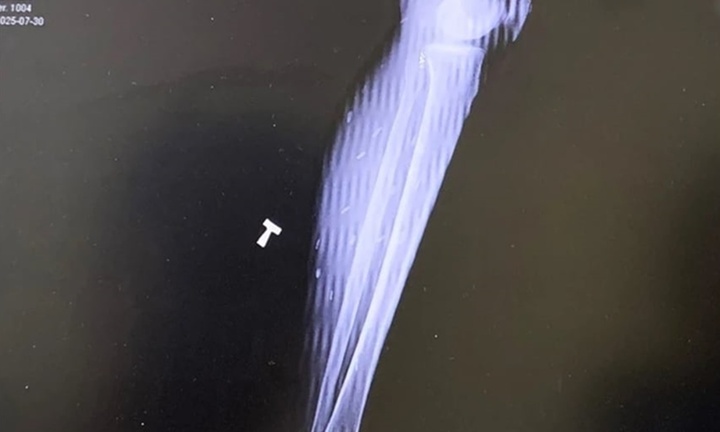

Sau nhiều năm mệt mỏi vì đau đầu, đau nhức cơ mà không tìm ra nguyên nhân, người bệnh mới được phát hiện trong cơ thể có sán dây ký sinh.